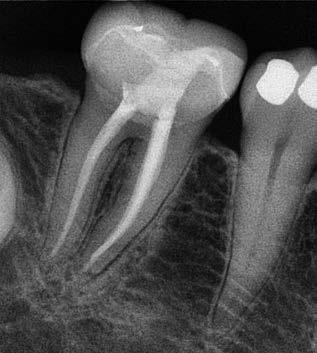

1. a-n. ábrák: Preoperatív CBCT-felvétel a bal alsó 6-os (3.6) fogról. Az axialis (a), coronalis (b) és sagittalis (c) nézeteken a mezialis és distalis gyökerek apicalis harmada körül sugáráteresztő zóna és ép buccalis corticalis csont látható. Egy olyan sablont terveztünk, amely jelezte a csontablak határait az apicalis terület pontos elérése érdekében (d). A mikrosebészeti bevatkozás során a sablont a helyére illesztettük (e), a csontablak határait megjelöltük (f) egy Piezotome CUBE LED kézi-darabba fogott fűrésszel, majd kivágtuk és eltávolítottuk (g és h) az apicalis területhez történő hozzáférés, illetve a mezialis és distalis gyökerek rezekciójának, retrográd preparációjának és retrográd gyökértömésének elvégzése érdekében (i). Végezetül a csontablakot visszaillesztettük és kollagén szivaccsal stabilizáltuk (j). A műtét után közvetlenül készített röntgenfelvétel a 3.6-os fogról (k). A kétéves kontroll során készített CBCT-felvétel: axialis (l), coronalis (m) és sagittalis (n) nézetek.

Egy 63 éves páciens korábban már kezelt bal alsó első nagyőrlőfogából (3.6) eredő mérsékelt fájdalom miatt kereste fel rendelőnket. A kórtörténetében panasza szempontjából releváns információ nem szerepelt. Az elkészült CBCT-felvételen a korábbi kezelések során észre nem vett, jelenleg feltáratlan meziobuccalis csatornát, valamint a mezialis és distalis gyökerek körül kialakult periapicalis elváltozást, és ezt a léziót borító intakt buccalis corticalis csontlemezt láttunk.

Klinikai vizsgálat során vertikális kopogtatási érzékenységet jelzett. A fog körül mérhető szondázási mélység és a fogmobilitás fiziológiás volt. A CBCT-felvételen nem észleltünk a csontos regeneráció megindulására utaló jeleket (1. a–c. ábrák). A korábban gyökérkezelt, gyökértömött és revideált 3.6-os fog esetében az alábbi diagnózis került felállításra: periodontitis periapicalis symptomatica. A panaszokat okozó fog további ellátása során navigált endodonciai mikrosebészetet kívántunk alkalmazni. Az alsó állcsontról intraorális szkent (TRIOS, 3Shape) készítettünk, és a felszíni topográfiát tartalmazó STL fájlt, valamint a CBCT-felvétel készítése során nyert DICOM fájlokat a Blue Sky Bio szoftver segítségével egyesítettük. A sebészi sablon megtervezésére az így kapott háromdimenziós képet használtuk. A sablon kialakítása során arra törekedtünk, hogy a sablon egyértelműen meghatározza a gyökércsúcsi terület eléréséhez szükséges csontablak határait (1. d. ábra)